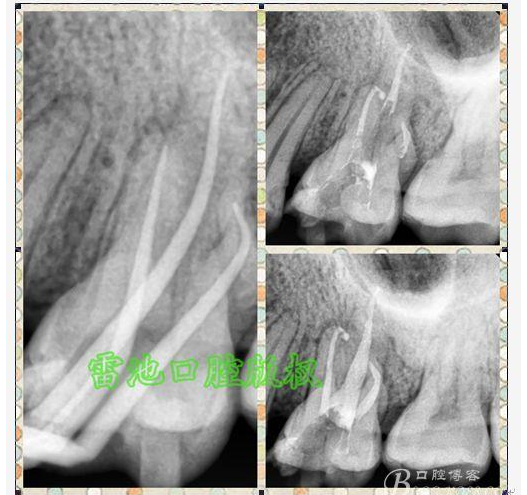

E 、X線影像學(xué)的檢查研判能力: 這點(diǎn)不需要強(qiáng)調(diào)太多,對于普通的非CBCT的二維影像對醫(yī)生讀片能力有一定的要求,有個(gè)逐步提高的過程,非一蹴而就,需要學(xué)會(huì)把二維的X線影像與三維的解剖結(jié)構(gòu)進(jìn)行良好的對應(yīng)結(jié)合,對于某些鈣化的髓室底,應(yīng)通過想象把根管口的分布、根管的走向以及各種變化通過想象投射到對應(yīng)的髓室底上;

G:找尋MB2的問題:

1、查閱各種文獻(xiàn),MB2的發(fā)生率在52-96%之間,治療時(shí)遺漏是上頜磨牙根管治療失敗的主因,2、一般位于MB1根管口與腭根管口方向的0.5-5mm范圍內(nèi),而大多數(shù)都位于MB舌側(cè)的1-3mm處,其中2mm以內(nèi)占85.7%,3、MB1-P根管口連線與MB1-MB2根管口的連線夾角大部分(74.3%)在30度以內(nèi);4、MB2的尋找大部分需要去除相應(yīng)部位的牙本質(zhì);5、當(dāng)找到的MB根管口呈“長線型”且有深色凹線向舌側(cè),或者找到的MB根管口明顯偏頰多提示有MB2的可能;6、DOM(牙科手術(shù)顯微鏡)的使用有助于找尋MB2;

H、關(guān)于下磨牙MM根管的重視問題: